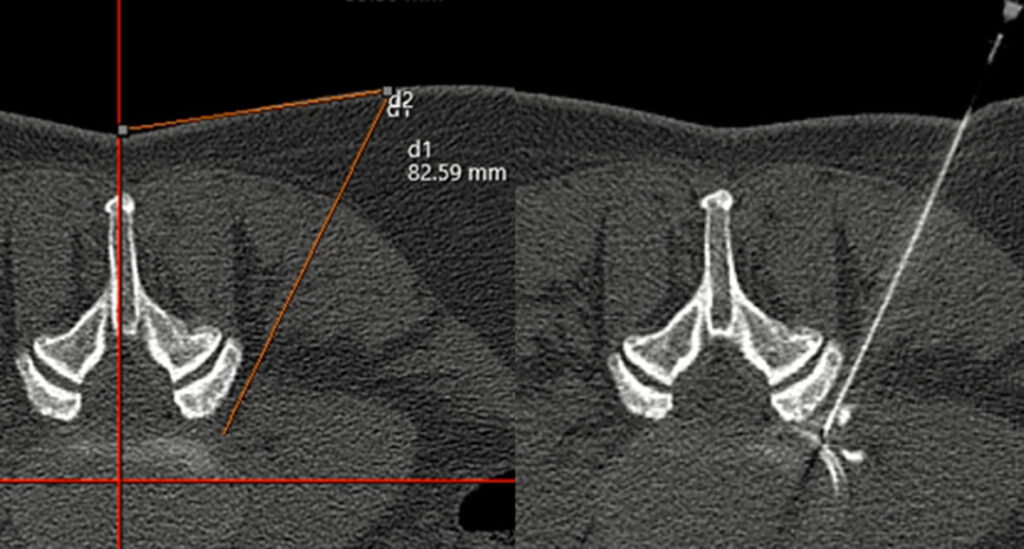

Das 0.55 Tesla MRT reduziert störende Bildverzerrungen durch Metallimplantate wie Prothesen oder Schrauben.

Präzise Diagnostik von Prothesen- und Schraubenlockerungen

Das MRT eignet sich besonders gut, um frühzeitig Lockerungen von Prothesen oder Schrauben zu erkennen. Es kann feinste Veränderungen an der Knochenstruktur oder an den Implantaten nachweisen, die auf eine Lockerung hinweisen könnten.